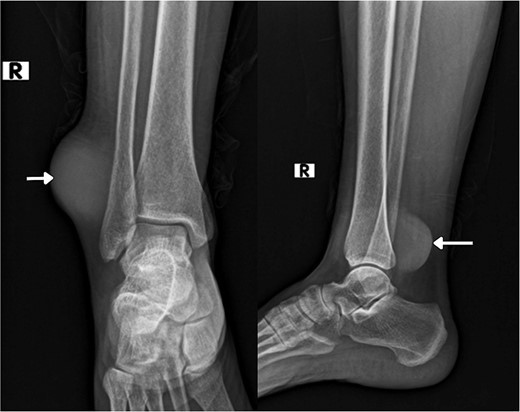

A physical examination showed a 4.5 × 7.5 cm oval mass was located at the right lateral malleolus (Fig. 1), which was firm, ill-defined, not adherent to the skin or the tissue underneath, not associated with any tenderness or hotness, negative trans-illumination test, and there were no palpable inguinal lymph nodes.

Gross views of the mass and the sural flap drawings at the operation table.

On imaging, an ankle X-ray showed an oval soft tissue mass subcutaneously at the level of the distal fibula (Fig. 2). The MRI showed about 5.7 × 3 × 5 cm of well-defined soft tissue mass within the distal lateral compartment of the lower leg, which seems locally invasive, abutting the fibular cortex, but without evidence of fibular cortical invasion (Supplementary Fig. 1). Moreover, a whole-body CT confirmed the absence of metastasis. CRP, ESR, LFT, and KFT were all within the normal range, and her bone profile was normal for her age. However, hemoglobin levels were slightly decreased (10.5 g/dl). An incisional biopsy showed features consistent with UPS. Therefore, the decision was to proceed with wide tumor resection and radiotherapy sessions.